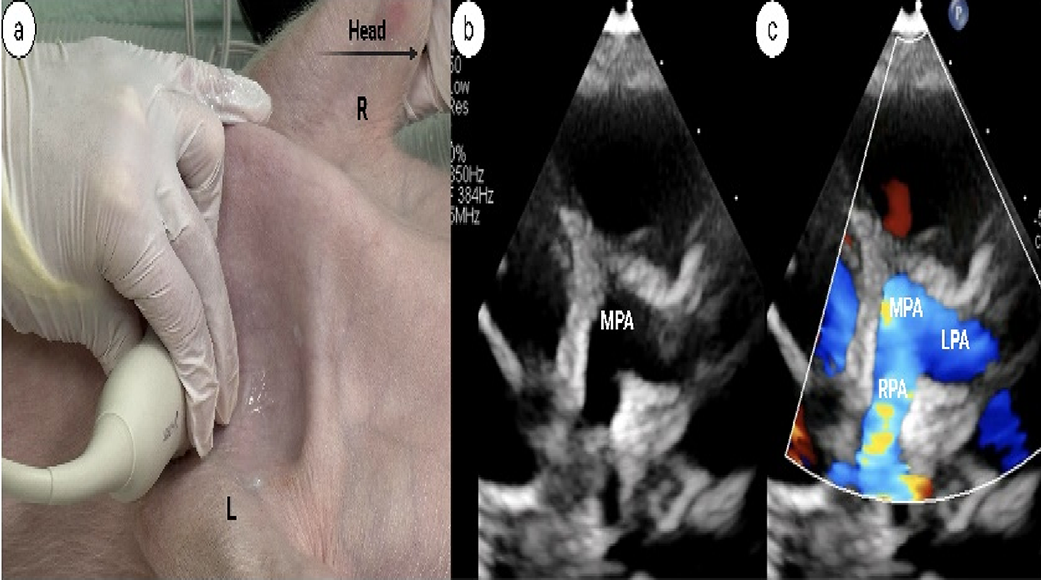

PDA view (Fig. 5a-c) | |

How to obtain: Supine position, probe positioned in the left axillary region, notch 1–3’oclock (Fig. 5a) • Evaluate branch pulmonary arteries by 2 d and color Doppler to look for patent ductus arteriosus (Fig. 5b-c) | |